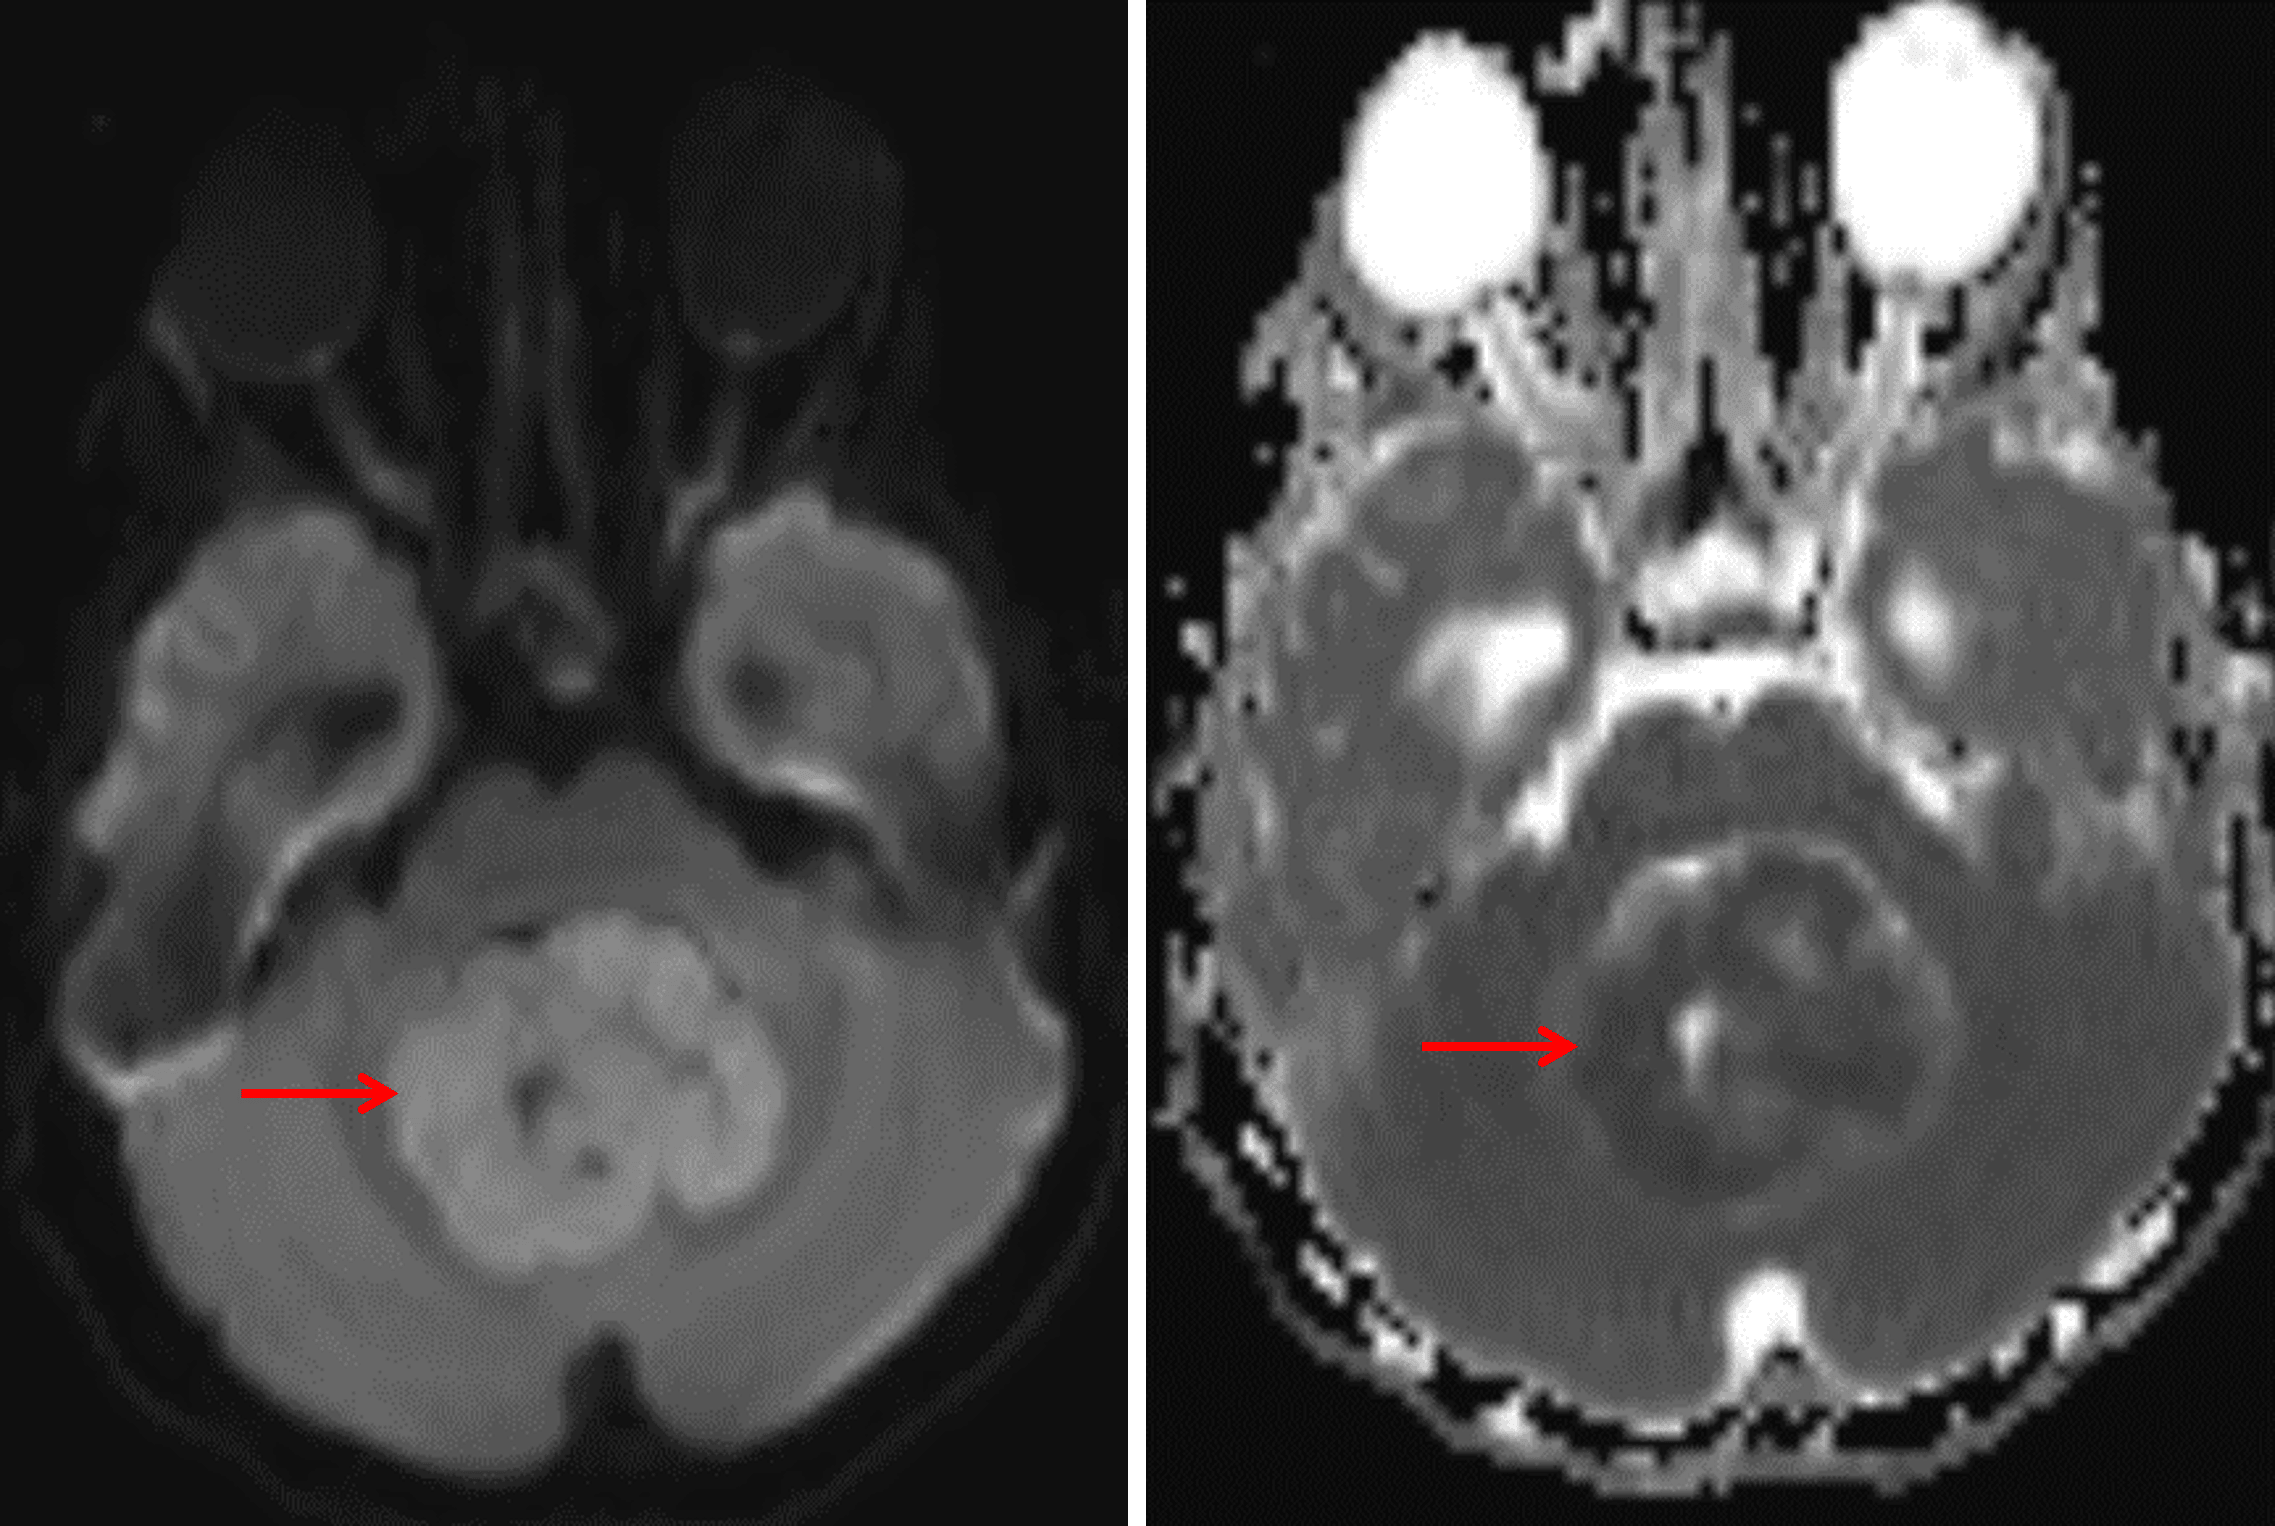

The tumor demonstrates diffuse corresponding restricted diffusion (red arrows), meaning hyperintense signal on the diffusion sequence (left) and hypointense signal on the ADC map (right).

• Heterogeneously enhancing mass centered in the fourth ventricle measuring 5 x 4 x 3 cm with associated diffuse restricted diffusion